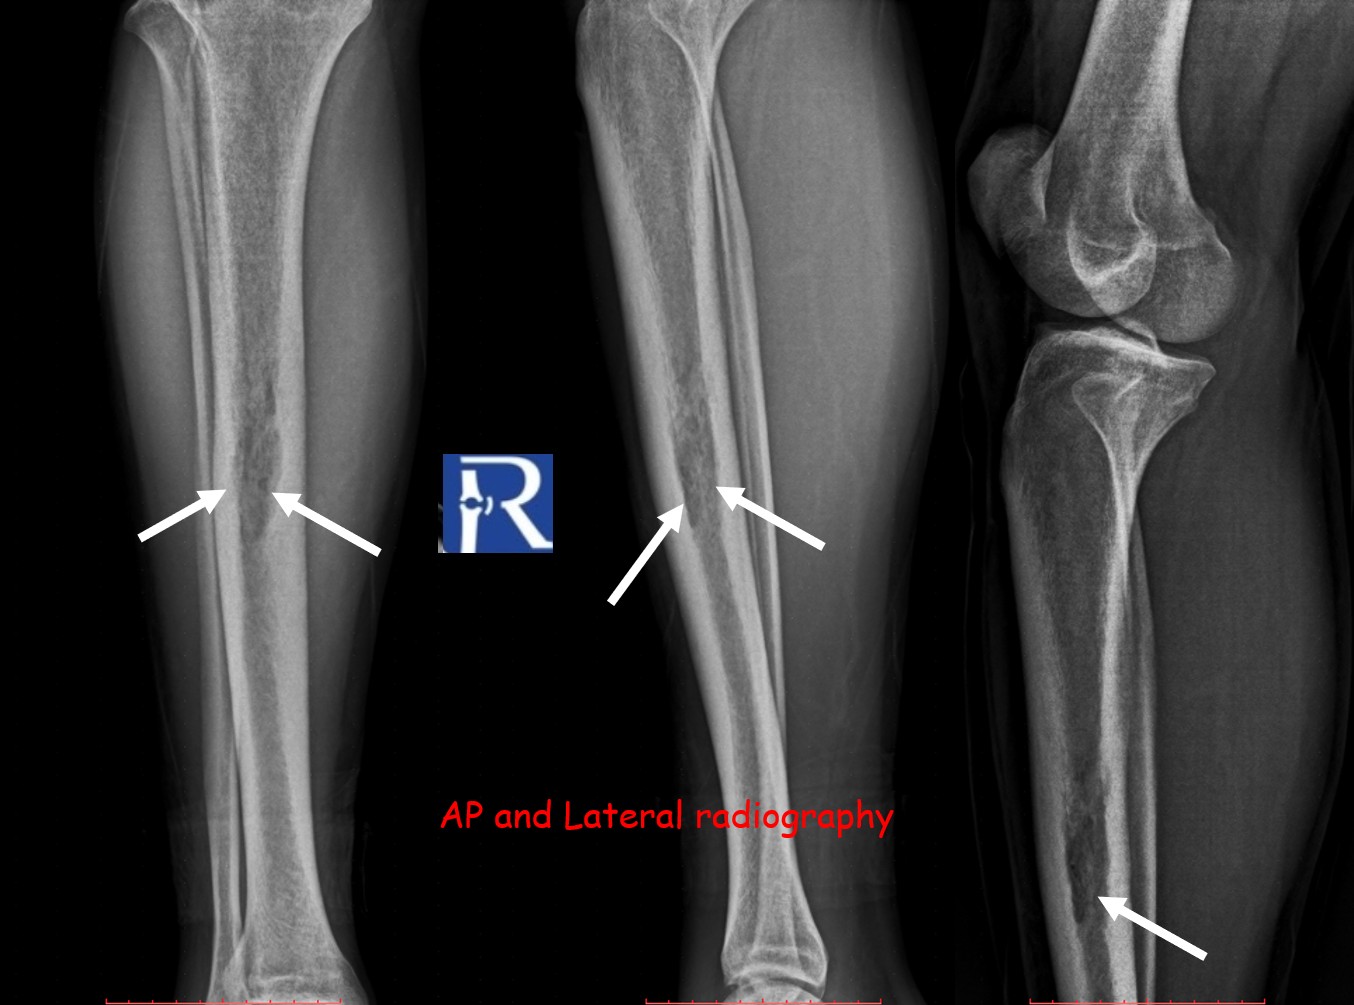

Plain radiography of the right tibia demonstrated a permeative lytic lesion at the mid-diaphysis, exhibiting aggressive characteristics but no periosteal reaction.

The lesion exhibited limited cortical destruction, yet extensive soft-tissue extension. Multiple conglomerate inguinal and pelvic lymph node enlargements were also identified, demonstrating signal characteristics similar to those of the primary lesion.

These imaging findings—particularly the absence of periosteal reaction, intermediate T2 signal, and marked DWI restriction—favored the diagnosis of lymphoma over Ewing sarcoma.